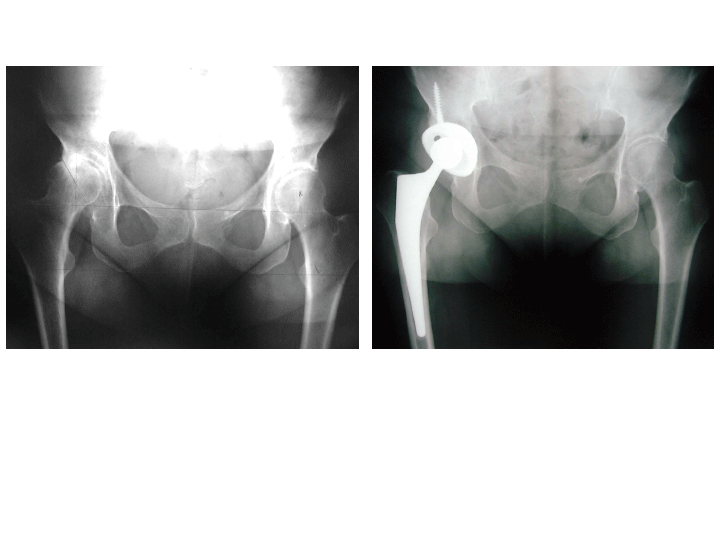

L’articulation de la hanche est composée d’une tête fémorale qui s’emboîte dans une cavité du bassin (le cotyle). La prothèse totale de hanche (PTH) remplace les surfaces articulaires de la hanche qui sont abîmée par la maladie (arthrose, rhumatisme inflammatoire, malformation congénitale, …). La PTH est composée d’une cupule hémicylindrique qui va s’emboiter dans le cotyle et d’une pièce fémorale. La pièce fémorale comprend une tige qui est implantée dans le fémur, surmontée d’un col et d’une tête qui s’articule avec la cupule. Le but de la PTH est de faire disparaître les phénomènes douloureux et de redonner une mobilité fonctionnelle à la hanche.

L’intervention consiste à implanter dans le fémur, un pivot métallique muni d’une tête et dans le bassin, en lieu et place du cotyle, une cupule cotyloïdienne. Le chirurgien choisira l’implant le mieux adapté à votre maladie et à votre gabarit en fonction des données de la science actuelle.